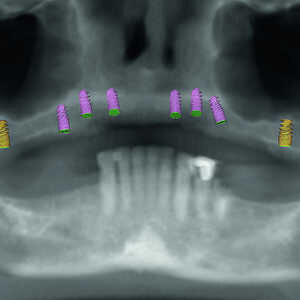

La patiente est revenue pour passer la visite des enregistrements. Au cours de celle-ci, des empreintes maxillaires et mandibulaires ont été prises afin de fabriquer des prothèses provisoires immédiates qui seraient mises en place lors de la visite prévue pour la chirurgie. Le scanner CS 8100 3D (Carestream Dental) a été utilisé pour acquérir des images CBCT, et obtenir ainsi les données nécessaires au plan de traitement virtuel. Les données 3D acquises grâce à la numérisation CBCT ont permis de déterminer les paramètres idéaux de longueur, de largeur et de positionnement des implants, aux endroits clés des arcades édentées de la patiente, soit les régions des premières molaires, premières prémolaires, canines et incisives centrales (Figs. 3–6). Des guides chirurgicaux à appui osseux maxillaire et mandibulaire ont été produits d’après le plan de traitement numérique conçu par 3D Diagnostix (Figs. 7 et 8).

Fig-5-Analyse-dento-faciale-du-traitement-implantaire-proposé-dans-l’arcade-maxillaire-300x300-

Fig-6-Analyse-dento-faciale-du-traitement-implantaire-proposé-dans-l’arcade-mandibulaire-300x300-